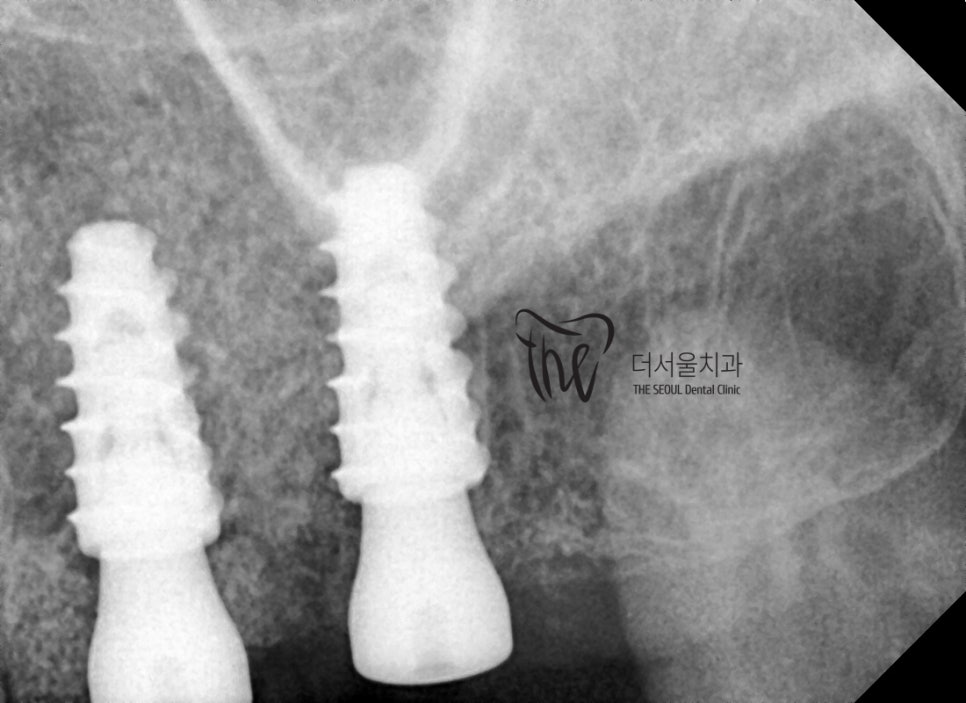

어금니 쪽은, 상악동거상술 및 뼈이식술을

같이 병행하면서 시술을 진행했습니다.

잘 심겨진 것을 볼 수 있죠?

어금니쪽에도 같이 재건이 이루어졌기 때문에,

앞니 임플란트 수술에 따른 심미성 개선 뿐만이

아니라 기능적 개선 또한 같이 도와 드렸던

케이스입니다.